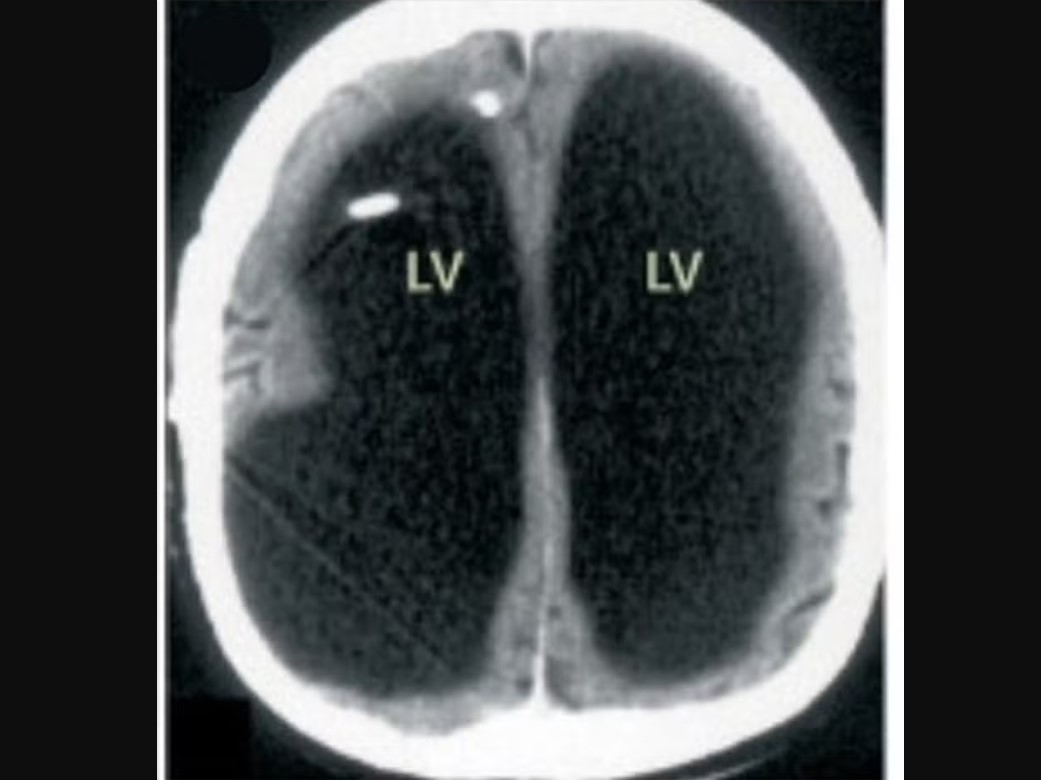

Depois que os médicos realizaram tomografias e ressonâncias, pois acreditavam que o paciente pudesse ter uma condição neurológica que estava afetando suas terminações nervosas, descobriram que, diferente do que pensavam, ele na verdade tinha uma enorme bolsa de líquido onde seu cérebro deveria estar.

Nas imagens de seu cérebro, compartilhadas com o periódico médico The Lancet, a parte principal de sua área cerebral aparece preta, que é onde havia acúmulo de fluido.

Isso fez com que seu cérebro se espremesse em uma camada estreita, que pressionava a borda do crânio.